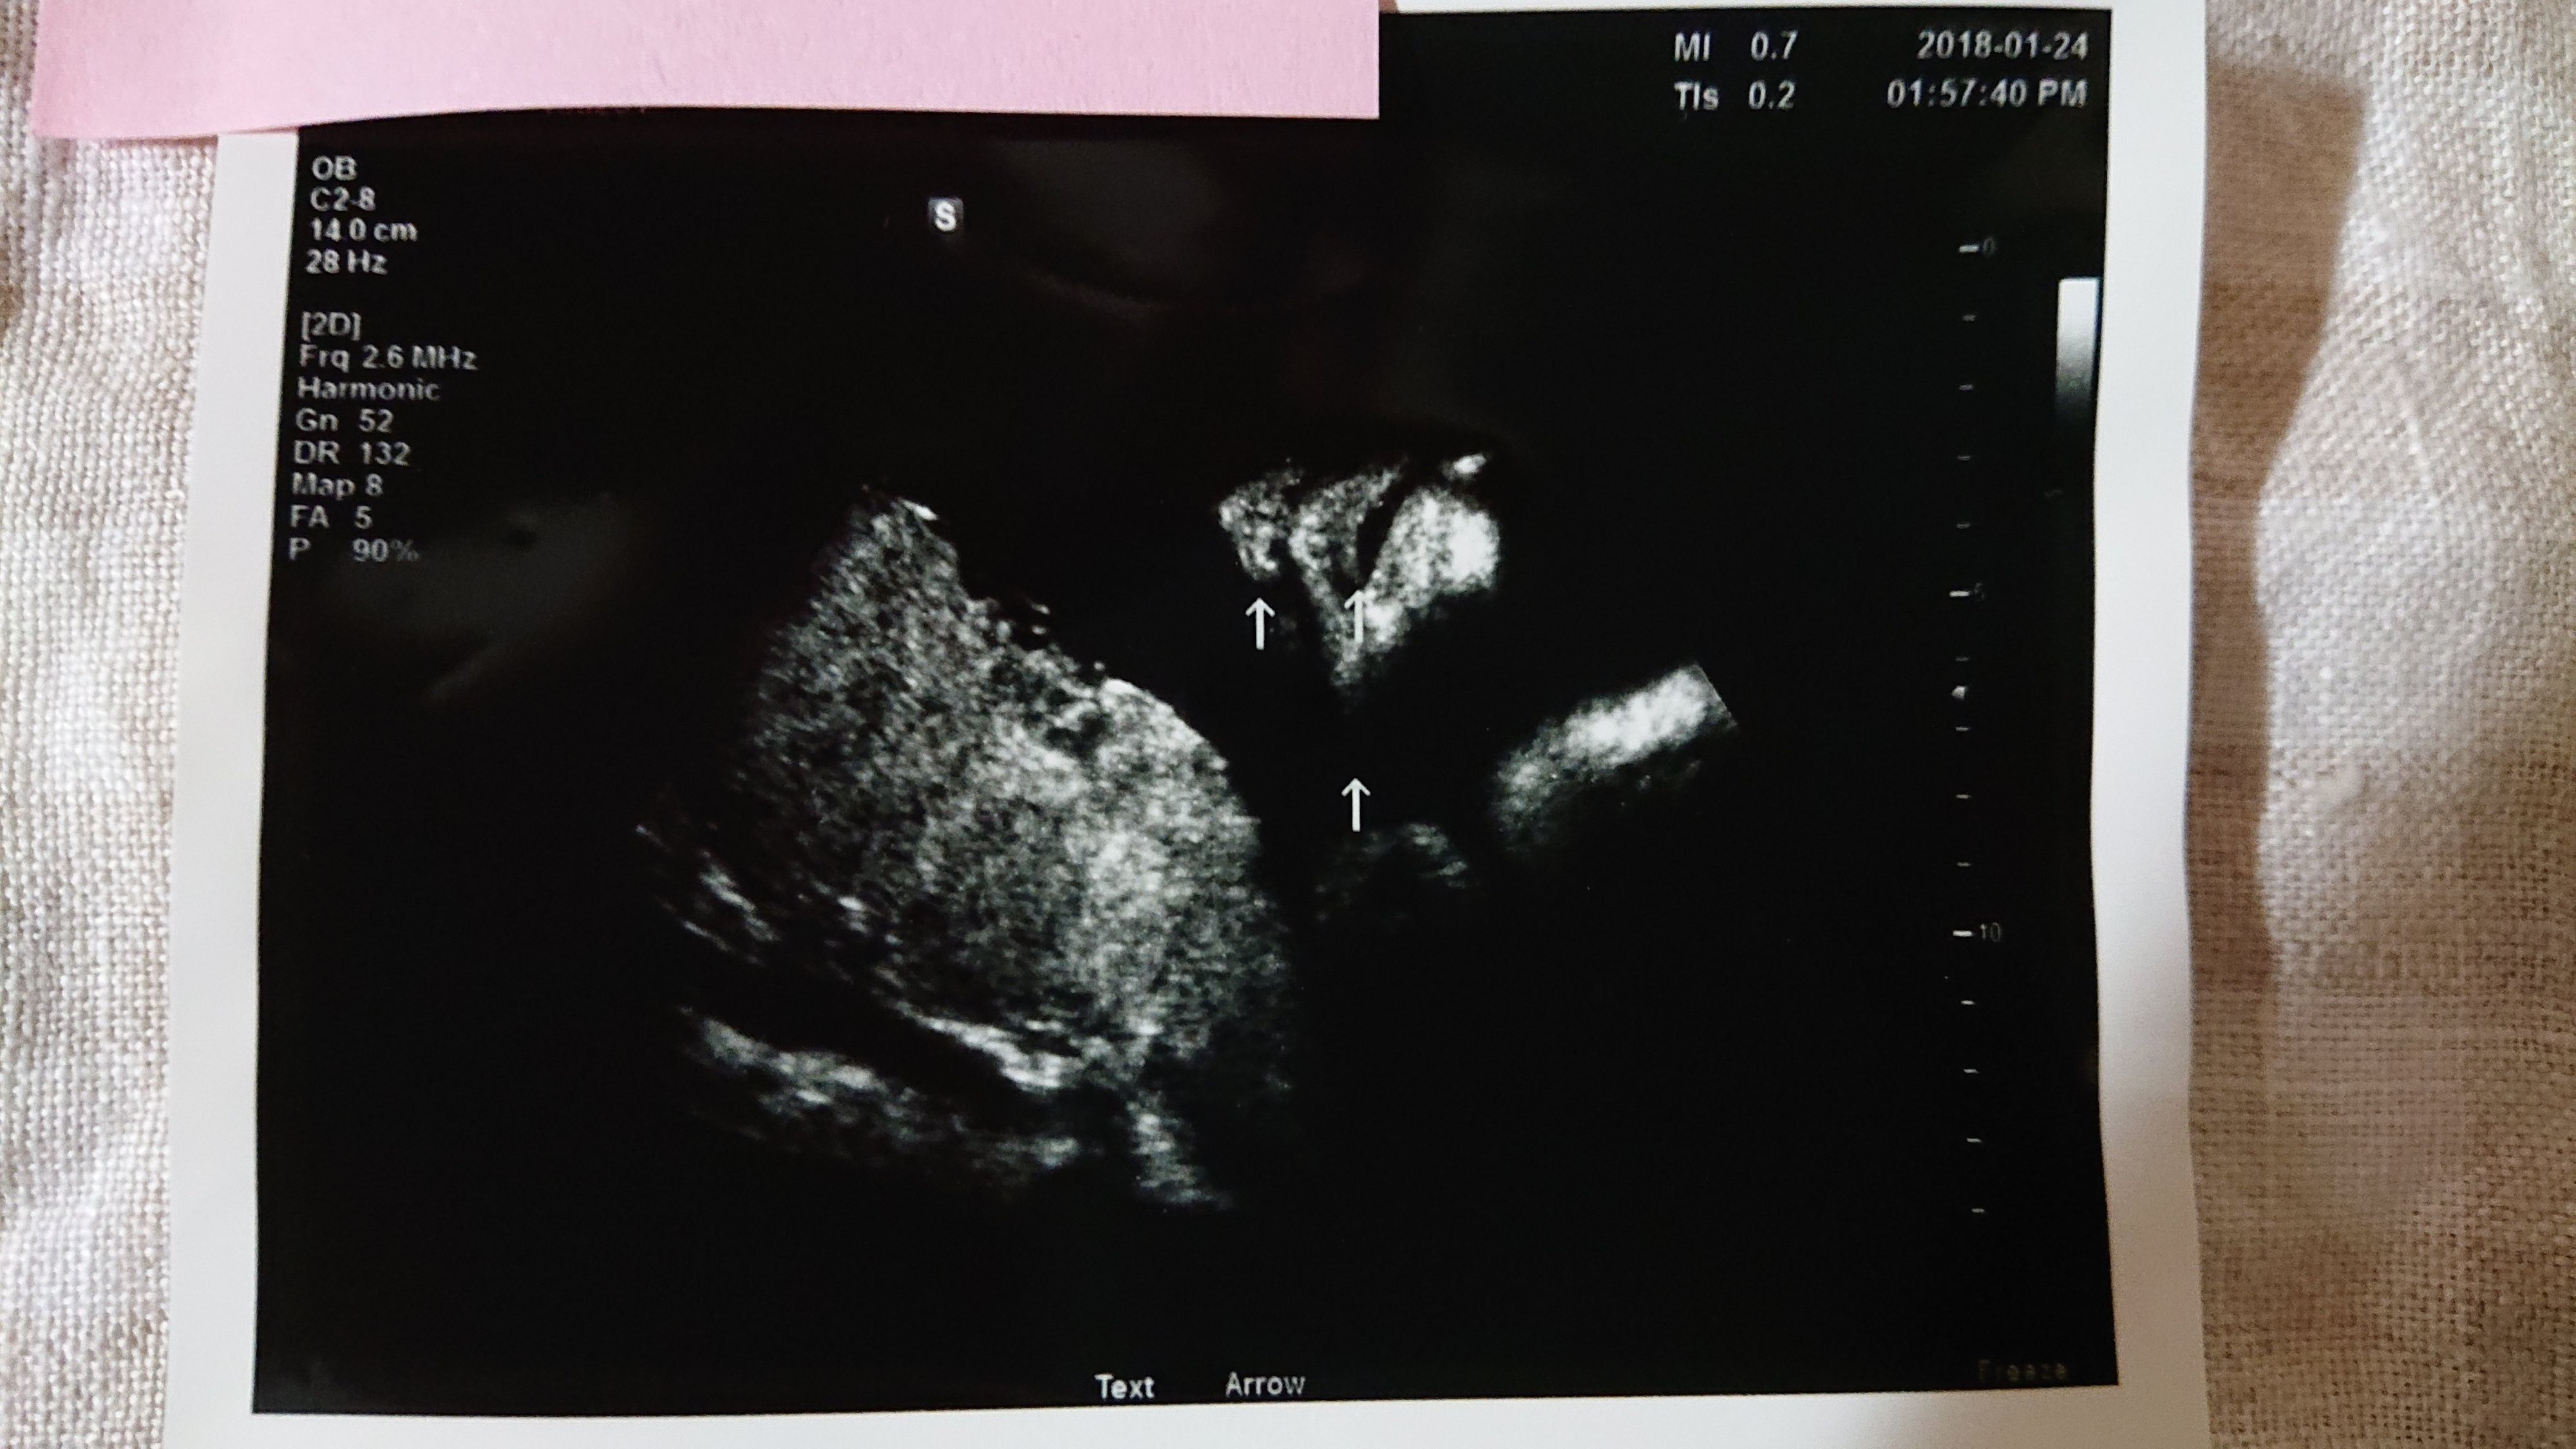

《妊娠30週目のエコー写真》

妊娠30週目、年内最後に受けた妊婦健診で頸管長が一気に短くなったことが判明。頸管長17mmとなり切迫早産の為、緊急入院しました。そして、なぜかこのタイミングで逆子になってしまいました。「赤ちゃんが、まわった感じしなかった?」と看護師に言われましたが、私にはサッパリ気が付きませんでした。その影響もあり、今まで全く頭になかった“帝王切開”の言葉を聞くことになりました。妊婦健診の後は、入院中のベッドの上で“帝王切開“を検索しまくりました。